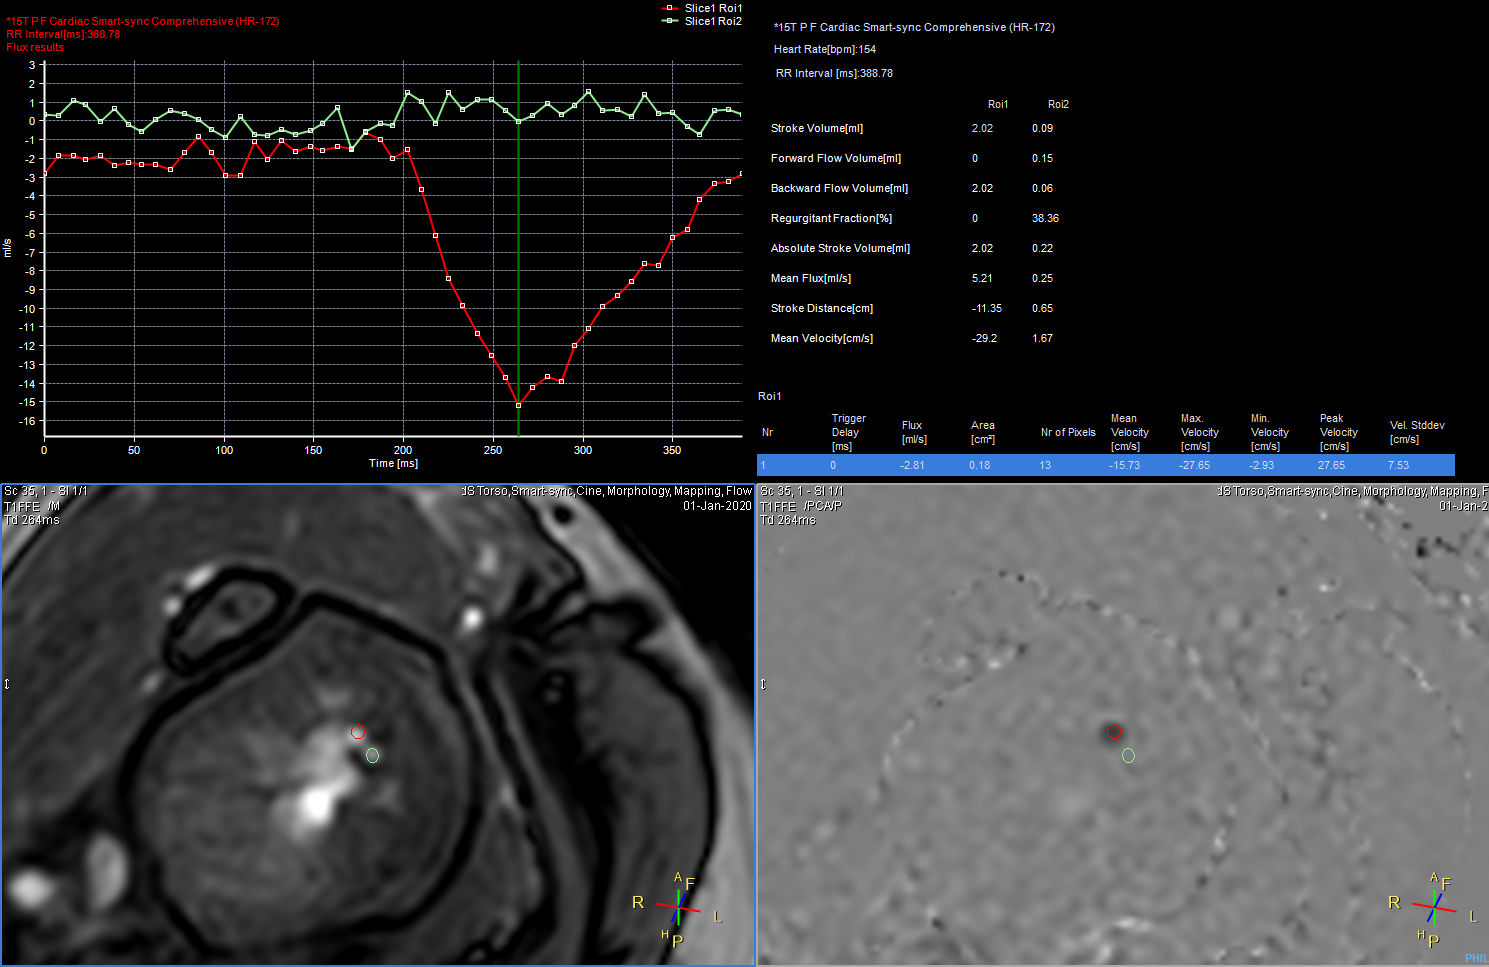

QFlow

Qflow analysis